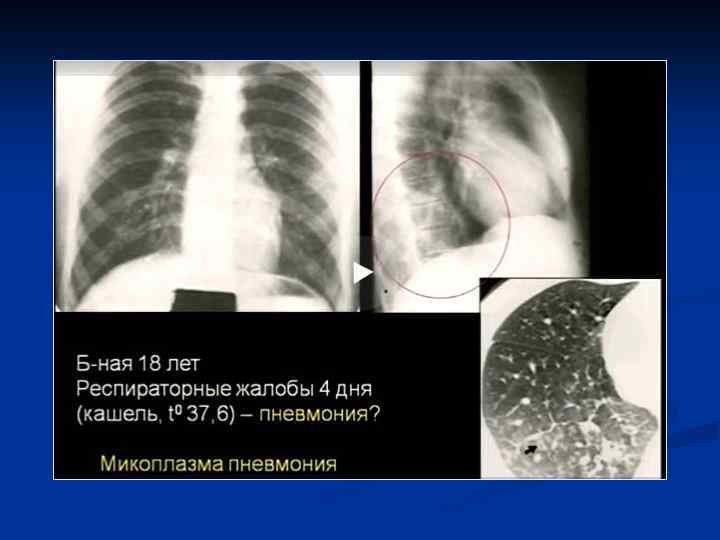

Интерстициальная пневмония n n n n Хуже диагностируются чем паренхиматозные Чаще – постгриппозные Вяло текут ОАК – почти норма Субфебрилитет Жалобы на недомогание, сухой кашель, вялость Это продуктивное воспаление (лечится тяжело)

Интерстициальная пневмония n n Характеризуется воспалительной инфильтрацией интерстиция Вызывающие ее микроорганизмы: вирусы, микоплазма, рикетсии, приводят к отеку и лимфацитарной инфильтрации стенок бронхов, Далее распространяется по междольковым перегородкам. Лимфоцитарная инфильтрация перибронхиальных альвеол, что придает сходство с очаговой ПН

Интерстициальная ПН - ретикулярные = сетчатые изменения легочного рисунка - преимущественно центральным = прикорневым распределением - могут быть очаговые сливающиеся уплотнения легочной ткани

КТ-семиотика интерстициальной пневмонии n n n Понижение прозрачности легочной паренхимы по типу «матового стекла» Утолщение внутридолькового интерстиция Утолщение междолькового интерстиция Утолщение перибронховаскулярного интерстиция Тракционные бронхо- и бронхиолоэктазы Изменения по типу «сотового легкого»

Клиническая картина Типичная - острое начало - лихорадка - кашель с обильной гнойной мокротой, влажные хрипы - боли в грудной клетке Атипичная - постепенное начало - сухой непродуктивный кашель - недомогание - першение в горле - миалгия - головные боли

ИТАК, n Долевые и очаговые инфильтративные изменения обычно характерны для бактериальных пневмоний n Сетчатые интерстициальные изменения или сочетание инфильтративных и интерстициальных изменений типичны для пневмоний вирусной, микоплазменной, хламидийной и пневмоцистной природы, а милиарные поражения — для туберкулеза легких, генерализованного сальмонеллеза, грибковых поражений. n Инфильтративные или интерстициальные изменения в сочетании с лимфоаденопатией типичны для туберкулеза легких и пневмоний, вызванных грибами, микоплазмой, хламидиями, вирусами кори и ветряной оспы.